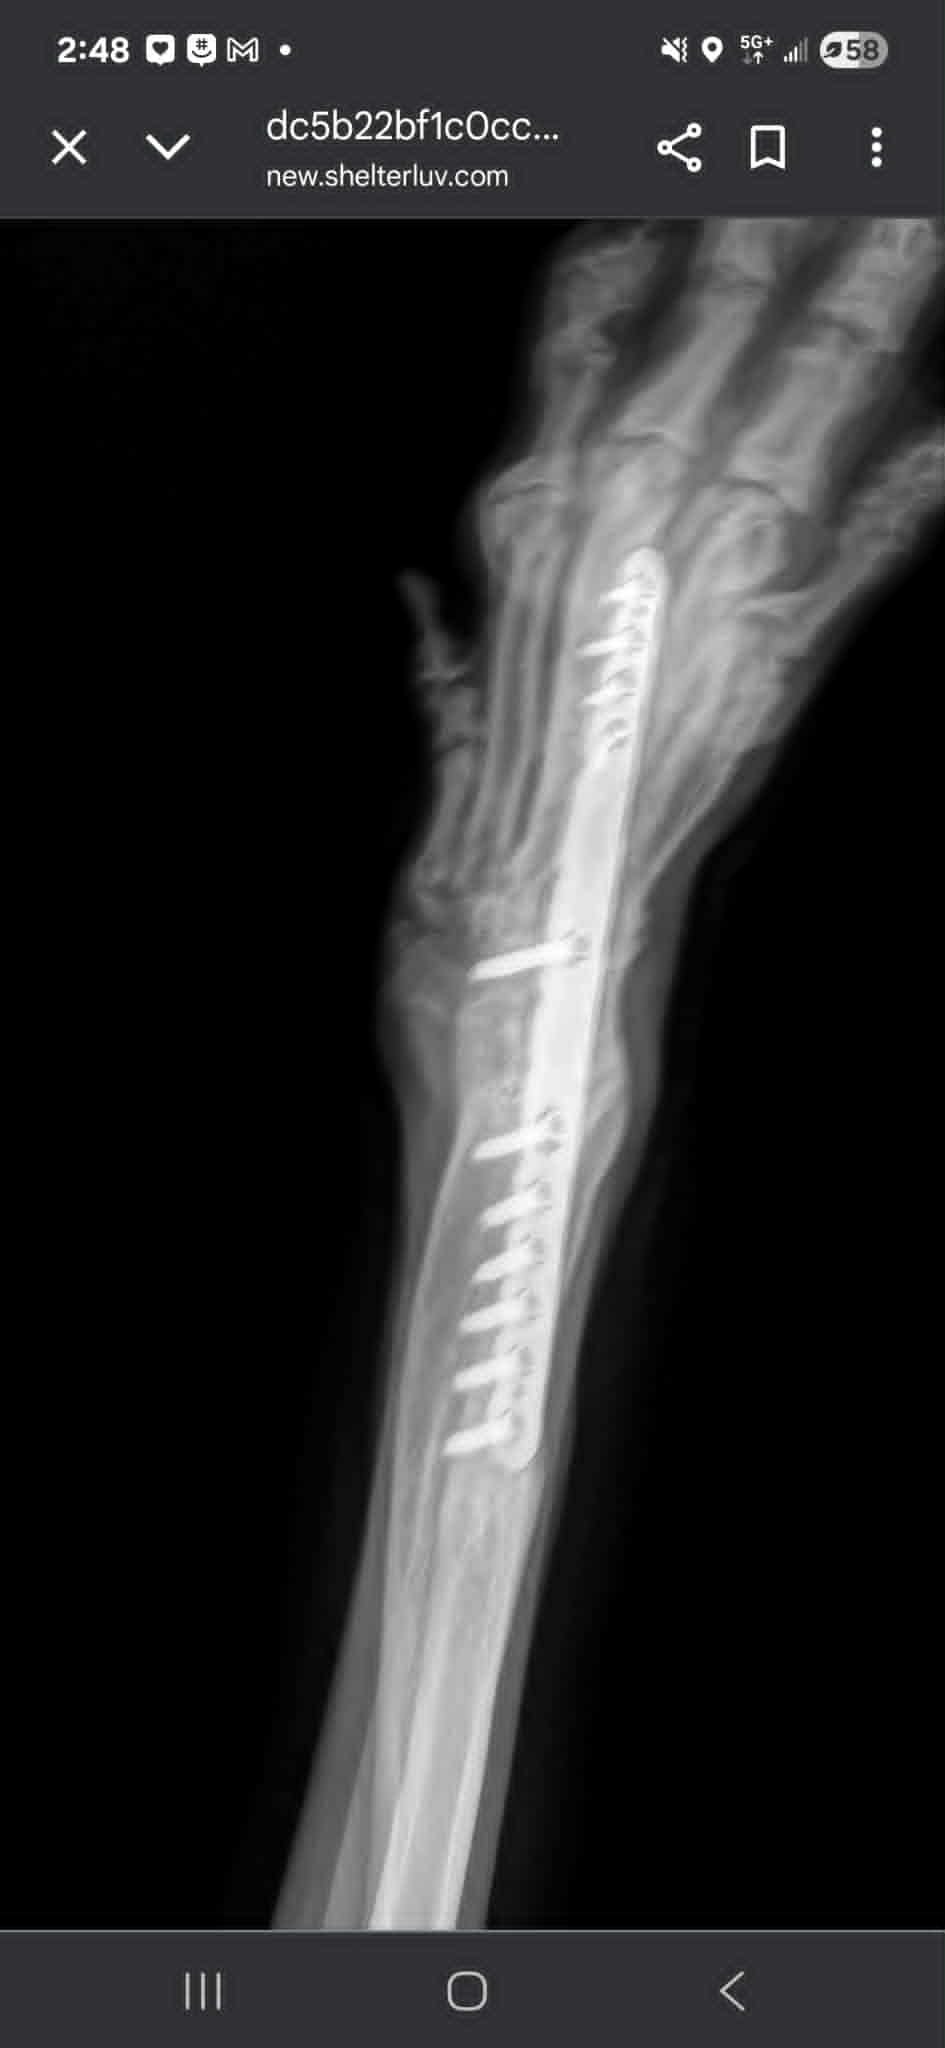

With Rown's fate seemingly sealed - somehow he found his way to an animal rescue where surgeries were performed to unblock and clear his stomach and stabilize his leg, which included the insertion of rods, pins and screws from his right paw pad up to his shoulder. He was flown to Border Tails Rescue in Northbrook in the hopes of finding a forever home, where he is currently being lovingly fostered by my mom, Pat. Rown (Shadow as she calls him) is doing great and is making progress with housebreaking, obedience, and is an excellent, excellent, dog who is very gentle and loving. My mom and Rown are a perfect match for each other and I wouldn't be surprised at all if she decides to adopt him. Actually, I really hope she does.

Shortly after she brought Rown home; however, my mom noticed that Rown began to favor his right leg and he developed a paw sore that would not heal. After additional medical care and a vet visit, it was determined that Rown's rod had shifted, which is now pushing down directly on the bottom of his paw pad, meaning Rown will require another surgery on his leg. We don't know what this will entail for Rown other than it will be extensive and will be an expensive cost for the Rescue to bear, which is why I am starting this GoFundMe. No matter what, we will do whatever it takes to support my mom and Rown during his recovery.